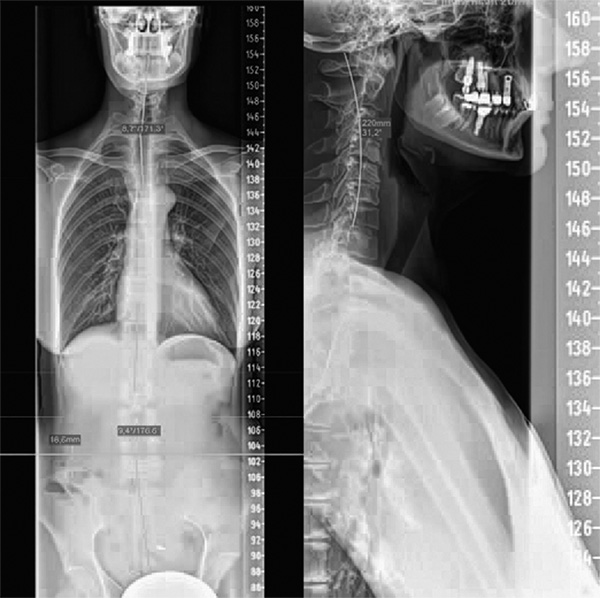

Ilustracja zamieszczona poniżej pokazuje jedną z możliwych przyczyn stresu oddziałującego na układ nerwowy. Nieprawidłowe ustawienia kręgosłupa prowadzą do mechanicznego stresu oraz odpowiedzi stresowej ze strony autonomicznego układu nerwowego (AUN). Szczególnie górny odcinek piersiowy – odpowiedzialny za współczulną część układu regulującego ciśnienie krwi – wykazuje wyraźne przemieszczenie powyżej 8°. Odcinek szyjny powinien mieć harmonijną krzywiznę (cienka linia), natomiast pacjentka ma odwróconą krzywiznę szyjną z wyraźną degeneracją krążków międzykręgowych. Prowadzi to do zwiększonego stresu w obrębie nerwu przywspółczulnego w górnym odcinku szyjnym. Można sobie wyobrazić, że organizm musi się dostosować do tej nietypowej sytuacji, między innymi poprzez podwyższenie ciśnienia krwi. Dzięki rekonstrukcyjnej terapii chiropraktycznej ciśnienie to udało się obniżyć do poziomu 120/80 bez konieczności stosowania leków. W ramach terapii poprawiła się także ruchomość odcinka szyjnego, zmniejszyły się objawy haluksa (Hallux valgus), poprawiła się jędrność skóry, ustąpiły bóle pleców, a także wyrównała się różnica długości nóg (wynosząca 16 mm po pomiarze na zdjęciu rentgenowskim.

Zdjęcie całości kręgosłupa od przodu oraz odcinka szyjnego kręgosłupa z boku. Zwraca uwagę nieprawidłowe ustawienie w górnym odcinku piersiowym oraz odwrócona krzywizna szyjnego odcinka kręgosłupa. Cienka biała linia przedstawia kształt zdrowego odcinka szyjnego (źródło: Praktyka lekarska dr. Meiera). Po zastosowaniu terapii chiropraktycznej objawy ustąpiły, a ciśnienie krwi spadło do 120/80.